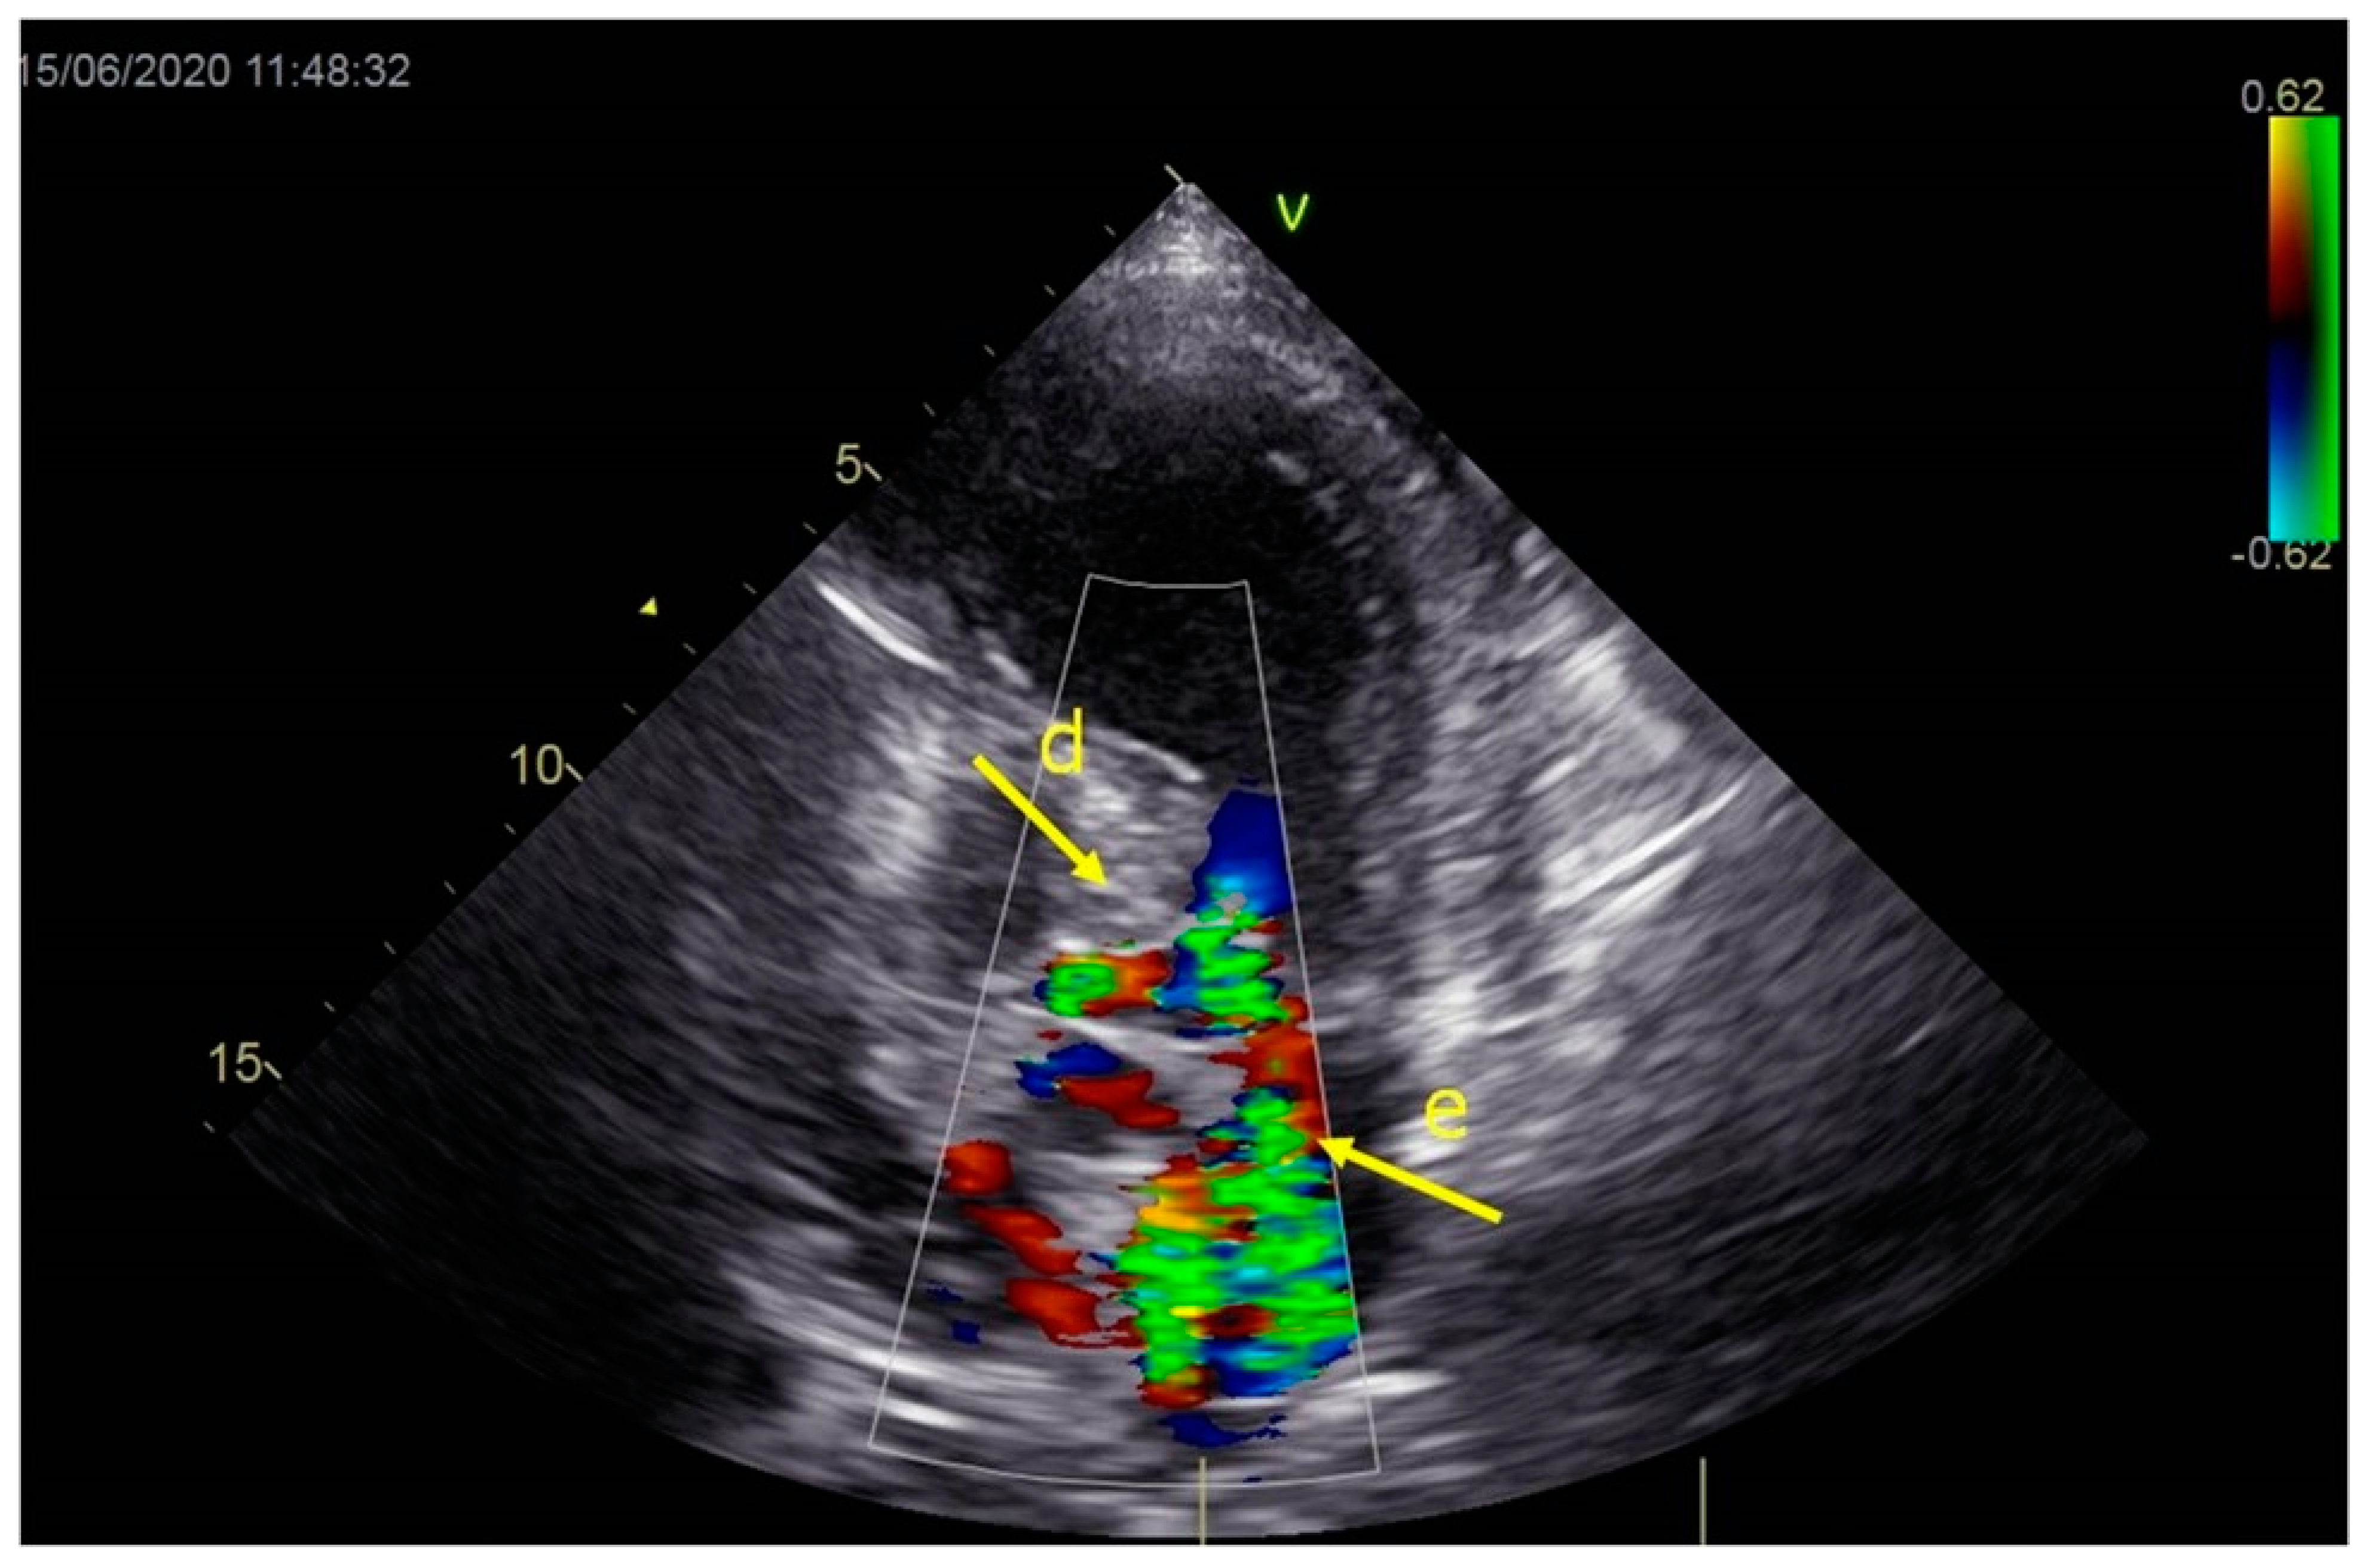

As a result, the patient was referred to a specialized medical institution. Upon admission, the patient was conscious, confused, hypotensive (TA 80/50 mmHg), with a heart rate of about 110/min, and showing clinical signs of hypoperfusion and cardiogenic shock, Killip IV. The medical staff administered sedation, inserted an endotracheal tube, and placed her on invasive mechanical ventilation. The patient was given crystalline solutions, inotrope, and vasopressor medication. An urgent echocardiographic examination was performed due to a rough systolic murmur over the precordium. It revealed akinesia of all medioapical segments of the left ventricle and akinesia basally inferior, where the myocardium was fibrously altered. Other hyperkinetic basal segments formed a dynamic obstruction of the left ventricular outflow tract (LVOTO) with turbulent flow and moderate mitral regurgitation (Figure 2 and Figure 3). The maximum gradient above the LVOT was 160 mmHg (Figure 4). The aortic valve area was 1.8 cm2 (Figure 5). The ejection fraction of the left ventricle (LVEF) was estimated to be 25%. The examination also revealed pericardial effusion with separation between pericardial layers along the right ventricle and atrium of up to 1.2 cm, but without any signs of tamponade.

Figure 2.

Echocardiography registered basal hyperkinetic segments of the left ventricle and formed a dynamic obstruction of the left ventricular outflow tract (a—LVOT, b—cuspi anterioris valvulae mitralis, c—aortic valve).

Figure 3.

Echocardiography registered moderate mitral regurgitation (d—LVOT, e—mitral regurgitation).